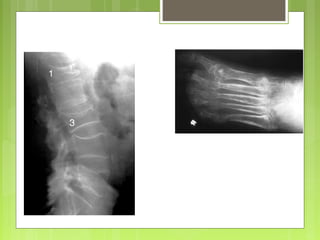

 Columna vertebral

 Granulomas eosinófilos

 Angiomas, quistes aneurismáticos, osteoblastomas,

cordomas

Columna Vertebral